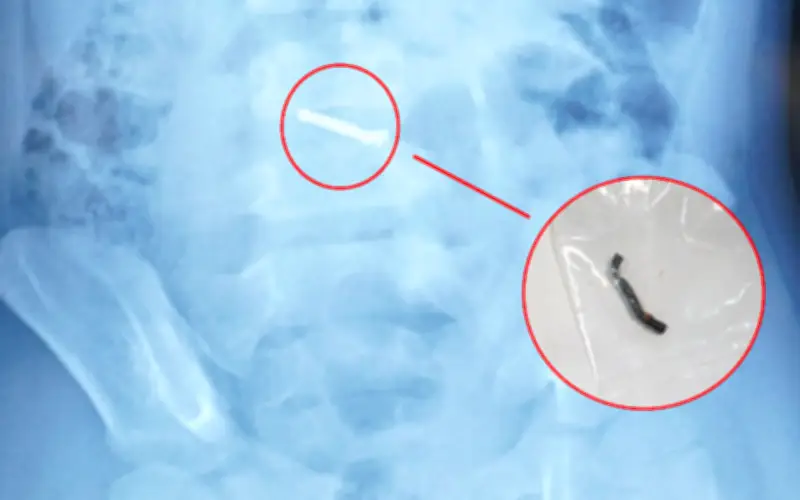

Lần này, qua chụp X-quang, các bác sĩ phát hiện có dị vật trong ổ bụng của bé. Ngay lập tức, trẻ được chuyển lên Bệnh viện Nhi Trung ương để tiếp tục theo dõi và điều trị chuyên sâu. Mẹ của bé chia sẻ rằng gia đình hoàn toàn không biết con đã nuốt dị vật từ khi nào, vì nghĩ rằng những khối nam châm xếp hình trong đồ chơi khá to và không thể nuốt được.

Tại Bệnh viện Nhi Trung ương, sau khi thực hiện các xét nghiệm và chẩn đoán hình ảnh cận lâm sàng, các bác sĩ nhận thấy dị vật trong đường tiêu hóa không di chuyển theo thời gian, trái với thông thường khi nhu động ruột sẽ đẩy dị vật ra ngoài. Từ thông tin gia đình cung cấp về loại đồ chơi có các viên nam châm nhỏ có thể hút vào nhau, các bác sĩ chẩn đoán trẻ đã nuốt phải nhiều viên nam châm trong nhiều thời điểm khác nhau.

Do dị vật có từ tính và không thể tự đào thải, các bác sĩ đã tiến hành phẫu thuật khẩn cấp. Trong quá trình mổ, họ phát hiện nhiều viên nam châm nhỏ đã dính vào nhau thành một chuỗi, gây ra lỗ thủng trên ruột của bé. Các bác sĩ đã nhanh chóng lấy dị vật, khâu lỗ thủng và đặt dẫn lưu để đảm bảo an toàn.